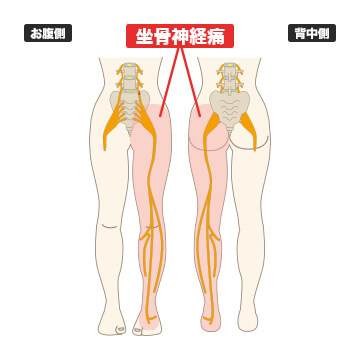

- 坐骨神経痛

坐骨神経痛とは、腰から足にかけて伸びる人体の中で一番太い神経に科学的炎症や圧迫といった刺激を受けることで現われる症状を指します。坐骨神経に炎症が生じることで、お尻や太もも、すね、ふくらはぎ、脚にかけて痺れや痛みを感じます。